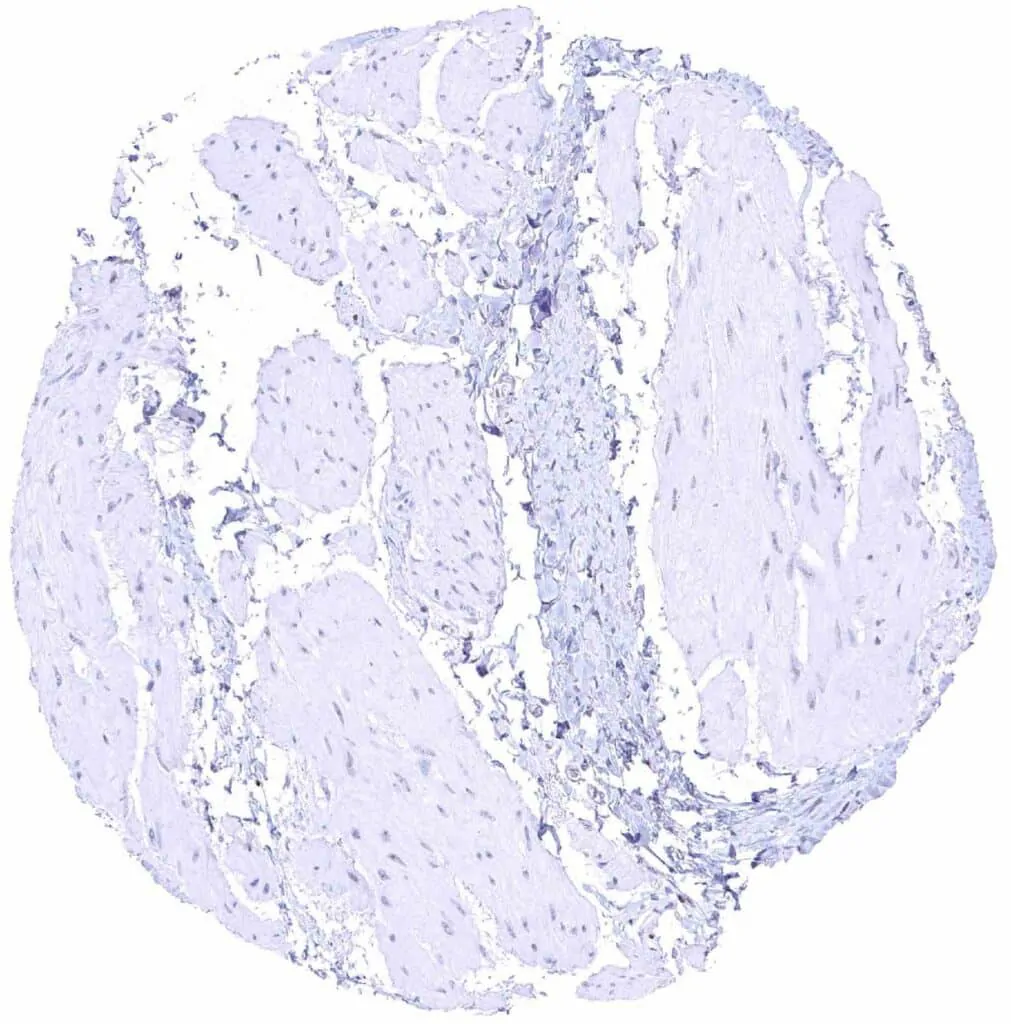

Fat